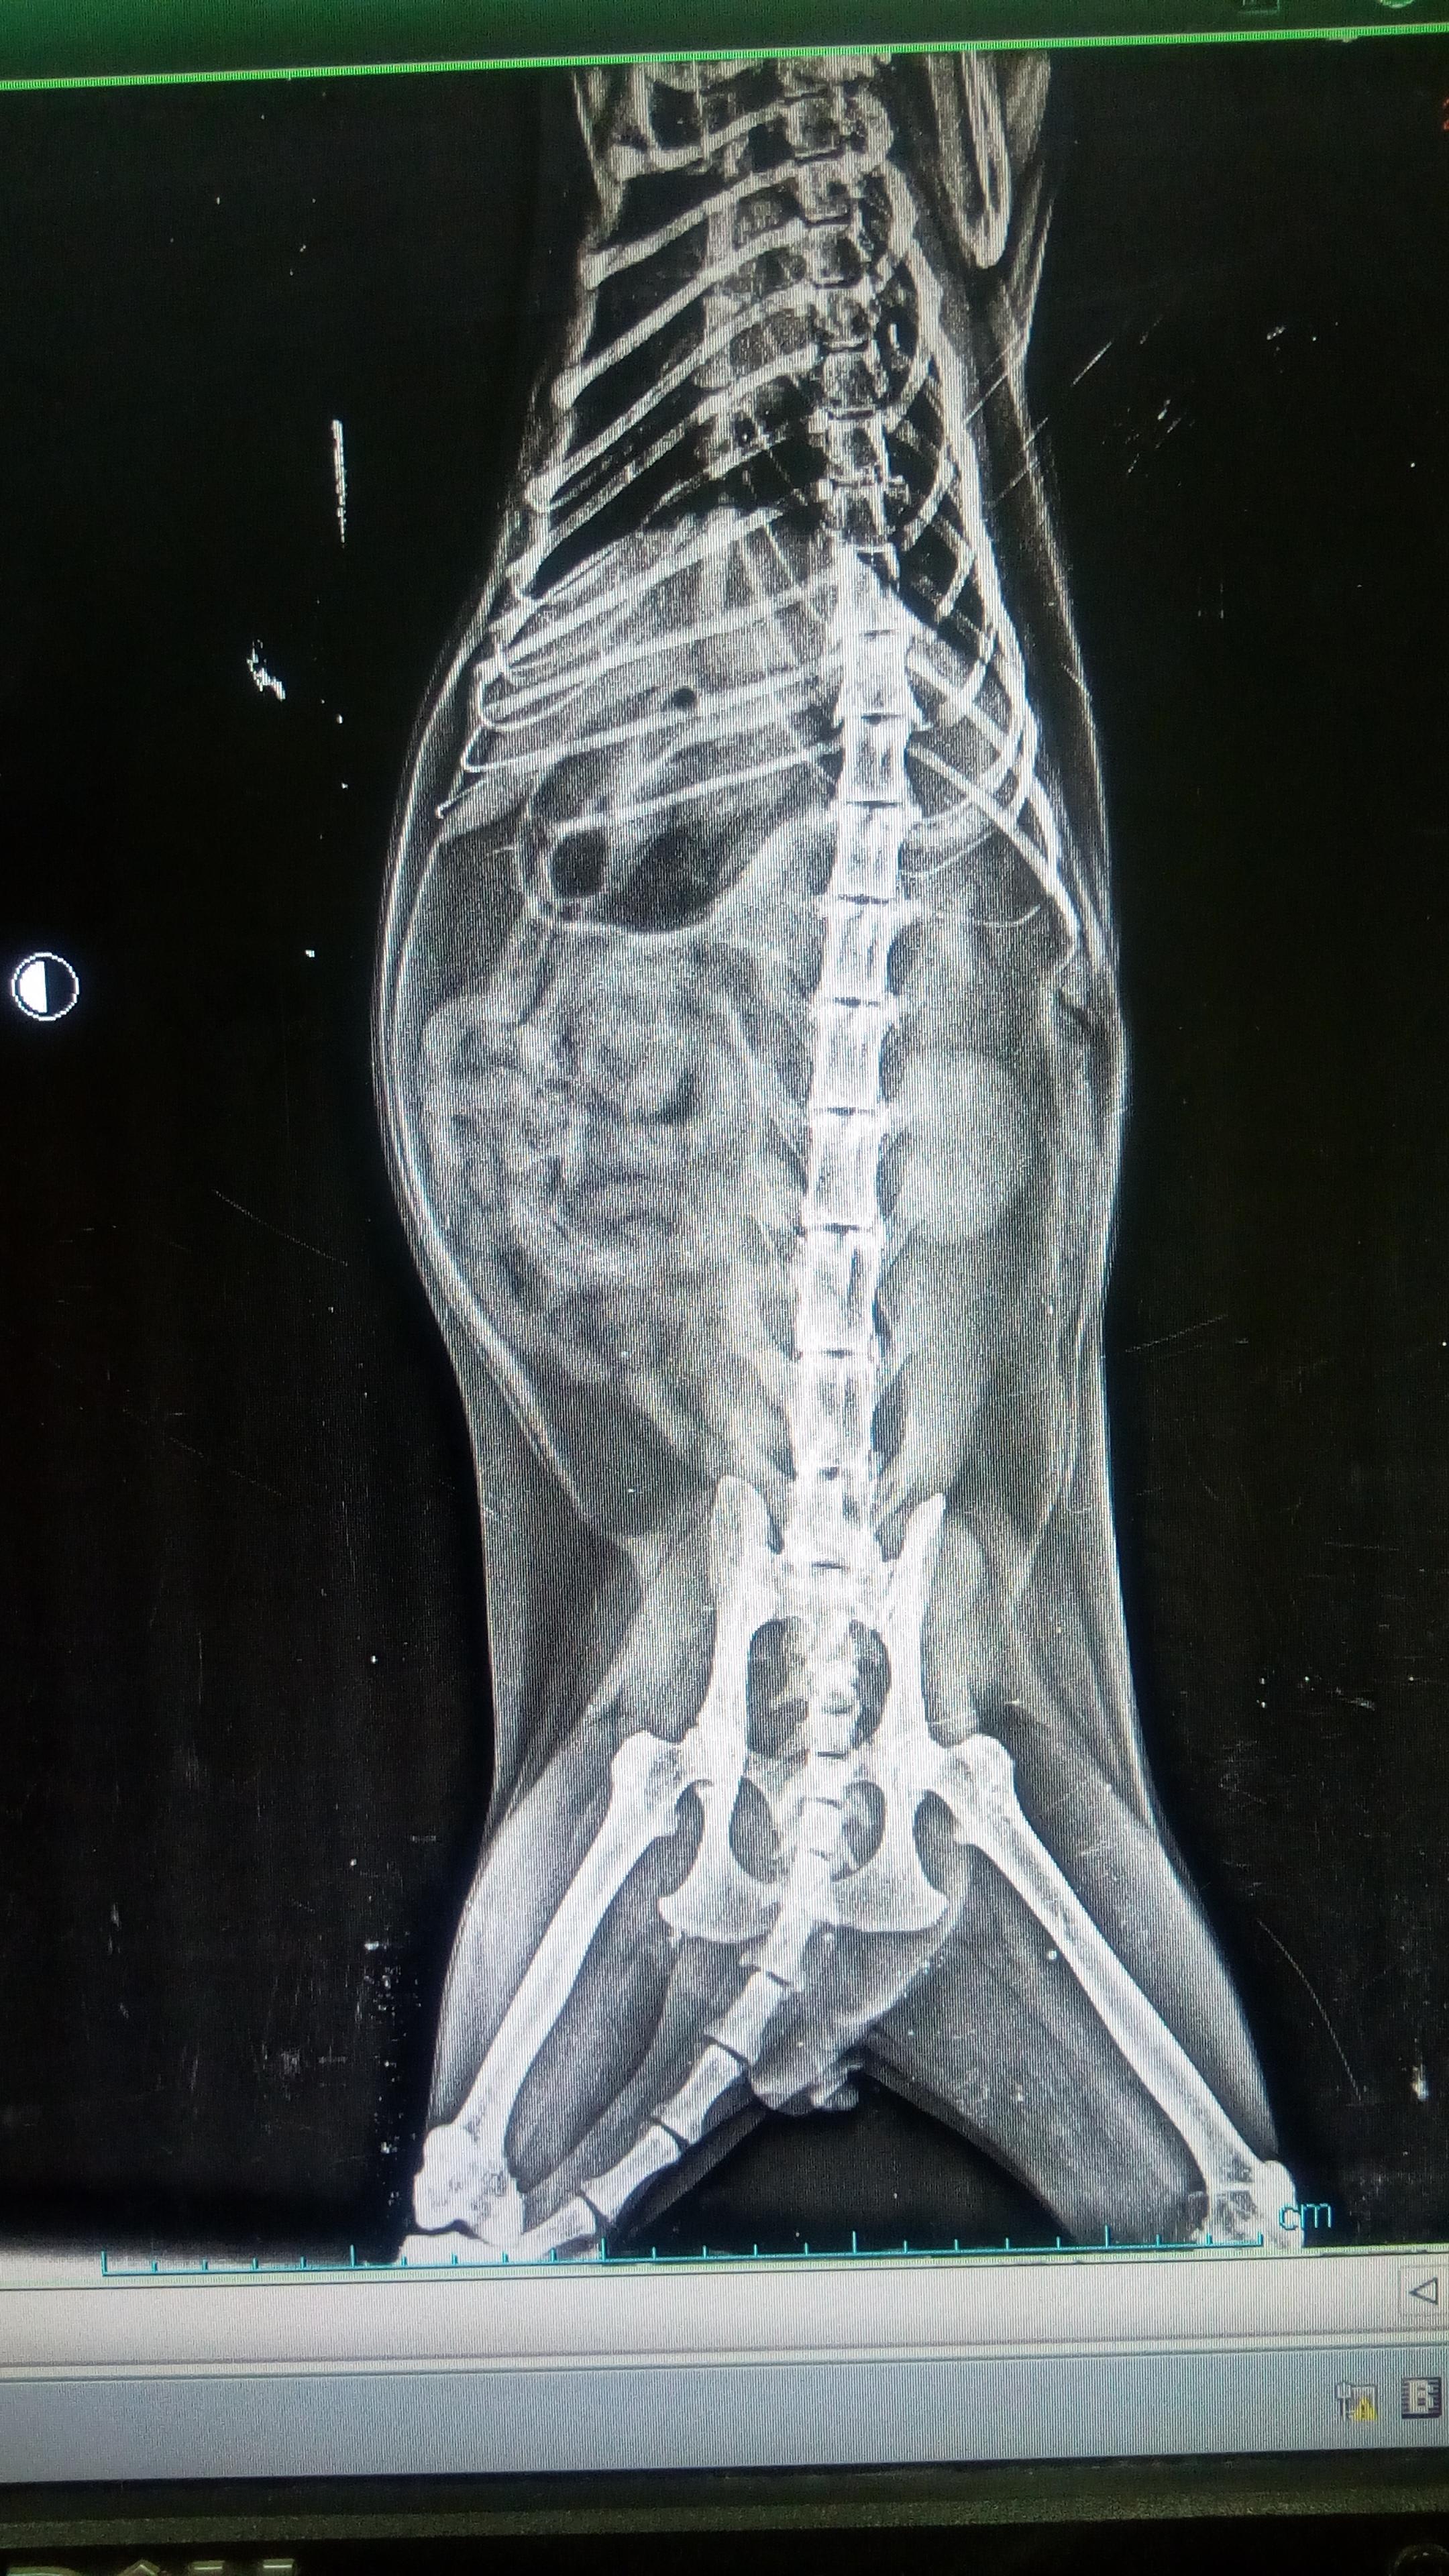

a week ago my cat stopped eating & started to throw up then he was drinking lots of water & throwing up an he did that constantly then he got hypothermia & started to shake and get dizzy & couldn't move so we took him to the vet he give him IV fluids to raise his temperature then he took x-ray of him & said that he have a severe gastritis and his Liver size is bigger a bit so he give him IV fluids & antibiotic for 3 days after that he did stop throw up but after 1 day he throw up again plz help

I am sorry for the delay in answering your question... I hope that Iomy is feeling better! Based on his xray, it does appear that his liver may be a bit enlarged. If he is still showing symptoms of illness, ask your family veterinarian about an abdominal ultrasound. This may help clarify what the problem is and what your options are. Also, if blood tests haven't been done that would also be helpful. Again, I hope you he is feeling better.... if you have additional questions please feel free to post on the forum and we will do our best to help!